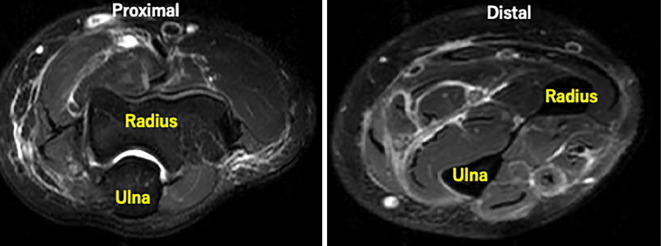

Restricted Movement Associated with Unilateral Diffuse Fasciitis.